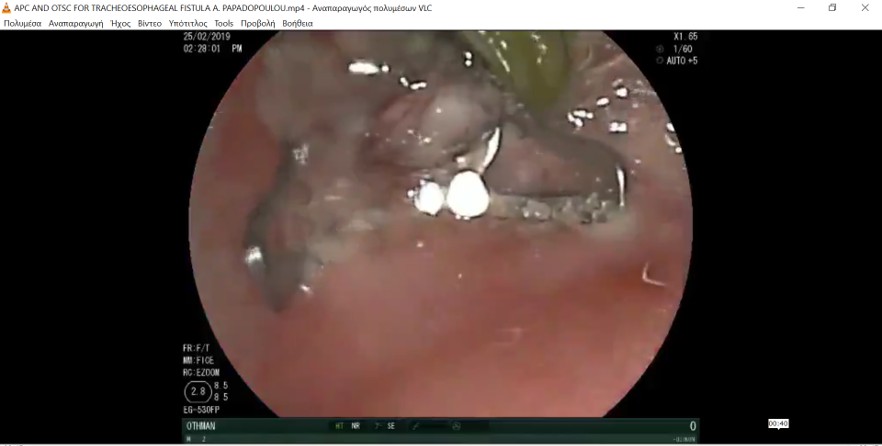

Καινοτόμες ενδοσκοπικές τεχνικές τις οποίες διενεργήσαμε με επιτυχία στο Νοσοκομείο Παίδων Η Αγία Σοφία για πρώτη φορά σε παιδιά στη χώρα μας